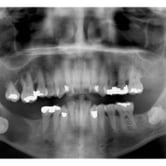

Quiste dentígero

Un quiste dentígero es un saco lleno de líquido que se forma alrededor de la corona de un diente no erupcionado.

Los pacientes pueden notar una hinchazón indolora en la mandíbula.

El tratamiento incluye la extirpación quirúrgica del quiste y, a veces, la extracción del diente involucrado.

Quiste odontogénico

Un quiste odontogénico es una lesión benigna que se desarrolla en los tejidos asociados con el desarrollo dental.

Los pacientes pueden experimentar hinchazón, dolor y movilidad dental.

El tratamiento incluye la extirpación quirúrgica del quiste y la evaluación para evitar recurrencias.

Dientes impactados

Los dientes impactados son dientes que no pueden erupcionar correctamente debido a la falta de espacio o a una obstrucción.

Los pacientes pueden notar que un diente no ha salido, aunque debería haberlo hecho. Esta condición es común con las muelas del juicio y los caninos superiores.

El tratamiento puede incluir la extracción del diente impactado o la creación de espacio para permitir su erupción.